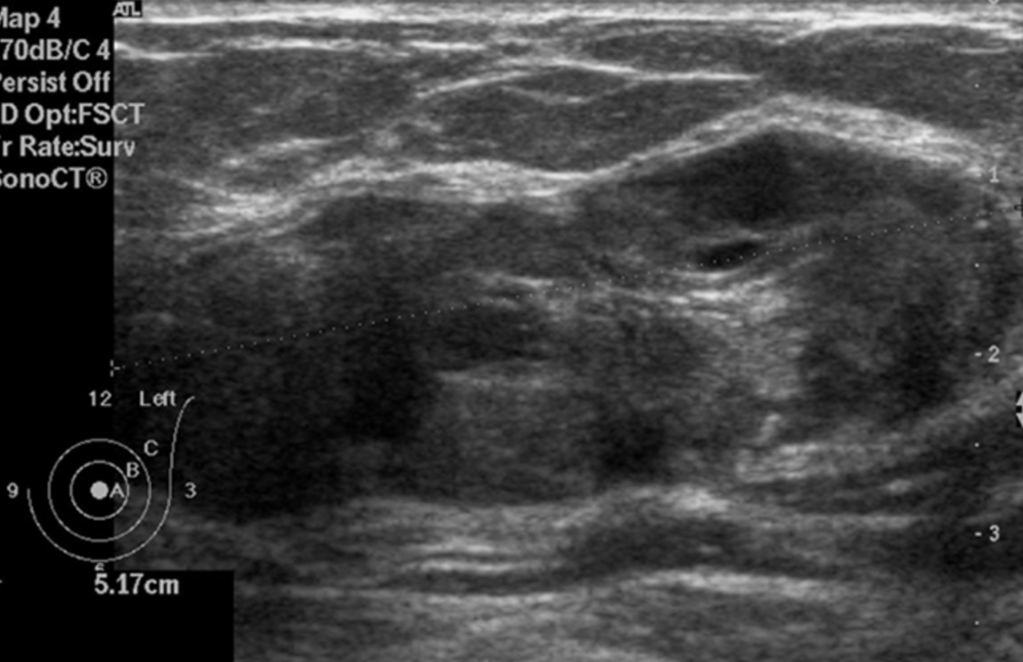

Image: Ultrasound of the left breast centered on the palpable lump showing an oval, heterogeneous lesions with smooth borders.

- On ultrasound:

- PASH tends to be:

- An oval, round hypoechoic mass or

- Can presents as a heterogeneous mass with cystic areas

- When a focal lesion with well-defined borders, containing no calcifications on mammography or a well-defined hypoechoic mass on ultrasound is seen:

- PASH can be considered and included in the differential diagnosis